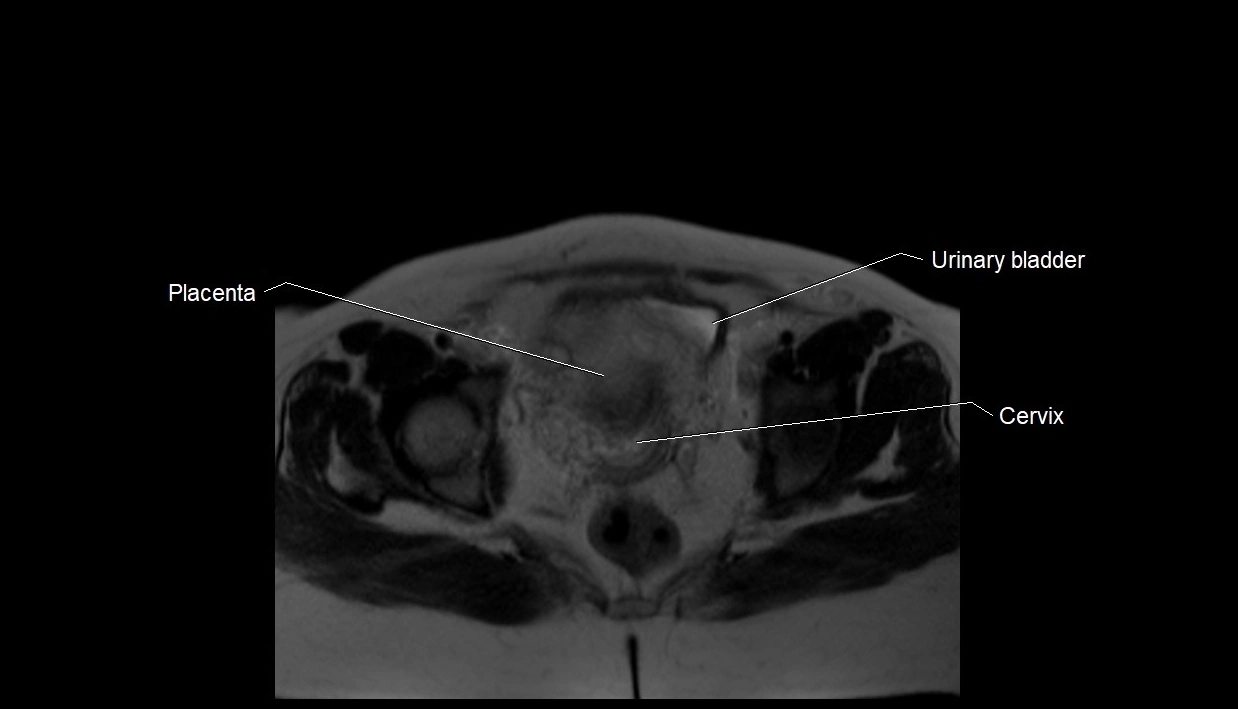

MRI Appearance

T1 GRE:

• Amniotic fluid shows low signal intensity (dark)

• Hemorrhage, infection, or proteinaceous content may cause focal or diffuse high signal intensity

MRI image

image